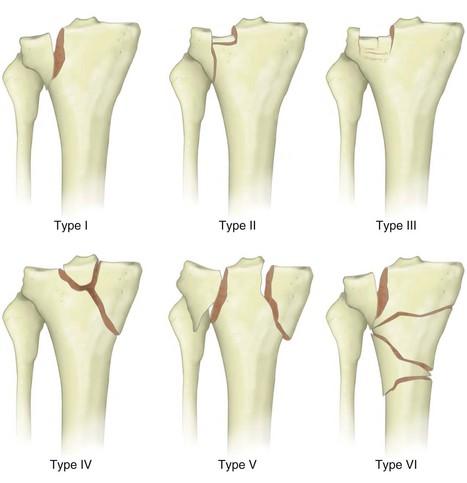

كسور نهاية الترقوة البعيدة هي إصابات شائعة تصيب الكتف، وغالبًا ما تحدث نتيجة السقوط أو الإصابة المباشرة. يعتمد أفضل عل…

كسور صفيحية الساق: التشريح، التصنيف، العلاج، والمضاعفات body { font-family: Arial, sans-se…